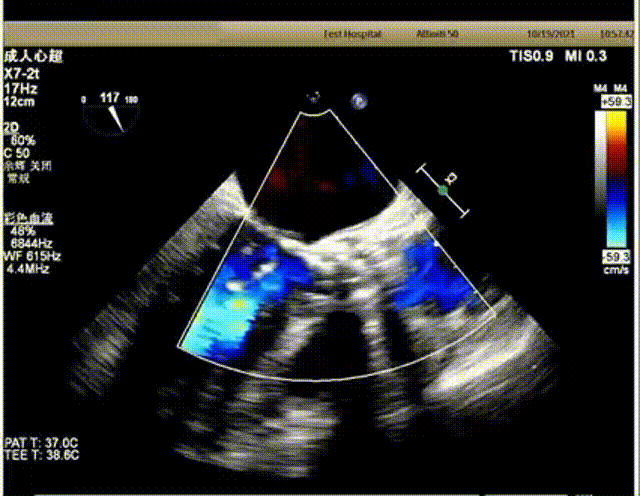

患者73岁、女性,胸痛十余年,加重一月,超声心动图显示主动脉瓣增厚,钙化,提示中重度狭窄并轻度关闭不全,EF值62%,主动脉瓣峰值流速4.2m/s,平均压差41mmHg。二尖瓣少量反流,三尖瓣少量反流。

超声下血流动力学良好,微量反流